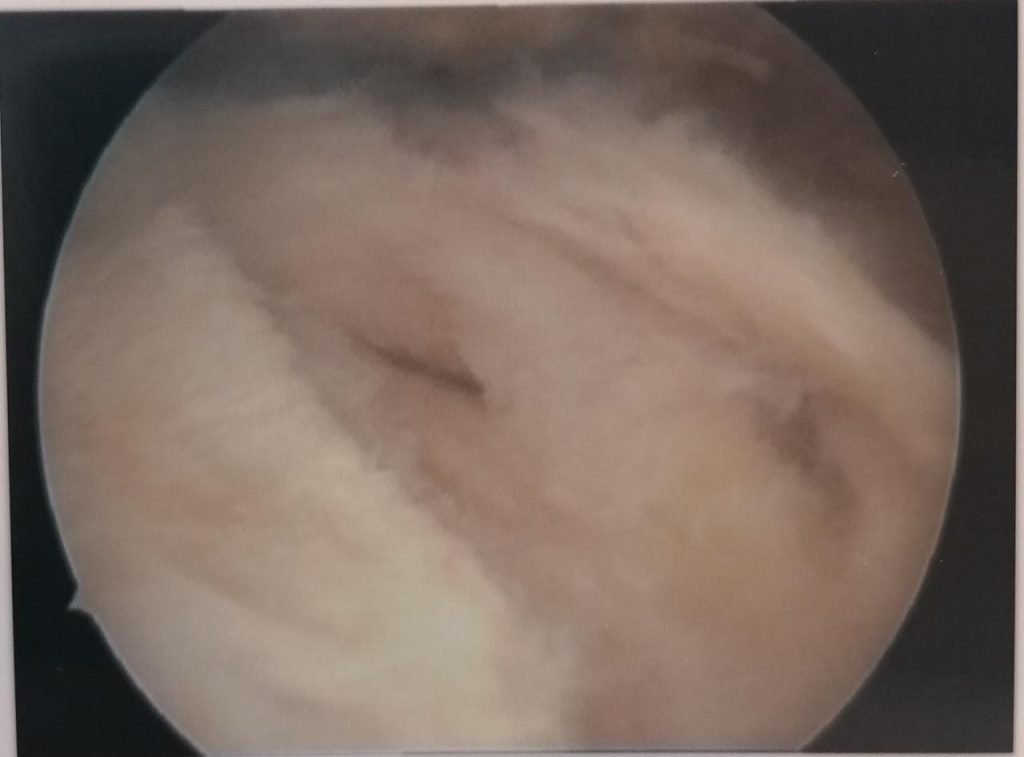

Above are pictures showing the placement of a suture through the edge of the capsule (labrum) to the placement of the anchor as well as the end result. All of this happens through two small incisions.

The rotator cuff is the confluence of four muscles that envelop the head of the humerus. It is responsible to initiate motion and to keep the humeral head centered in the glenoid. Age or trauma can cause tears of the rotator cuff, leading to pain and loss of function. Luckily it can be repaired arthroscopically with excellent results